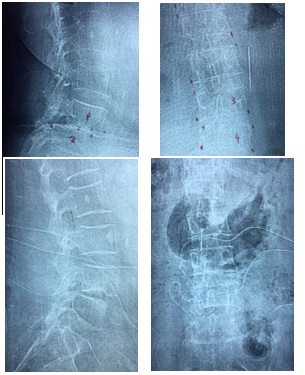

Gambar 6. Sebelum PSLD dan Sesudah PSLD, Pasien usia 55 tahun. |